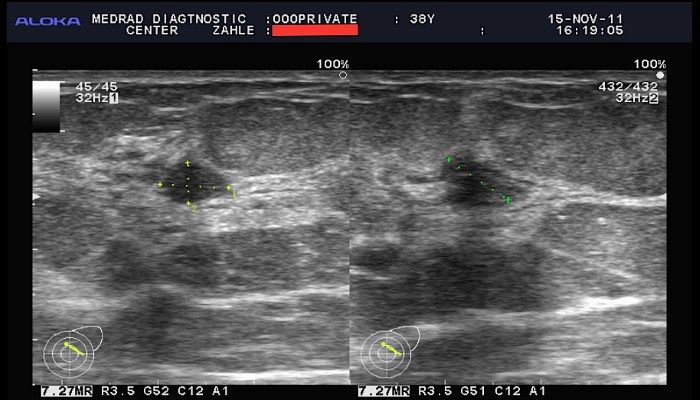

Помимо маммографии, может быть назначено УЗИ молочных желез. Эхография предоставляет менее точные данные о размере и форме, но помогает определить характер опухоли и исключить возможность рака. Для этой же цели может быть рекомендована биопсия – процедура, при которой берется образец содержимого опухоли для микроскопического исследования.

Диагностика аденоза обычно включает физический осмотр молочных желез врачом, а также использование методов визуализации, таких как ультразвуковое исследование или маммография. В некоторых случаях может потребоваться биопсия для подтверждения диагноза и исключения других заболеваний.